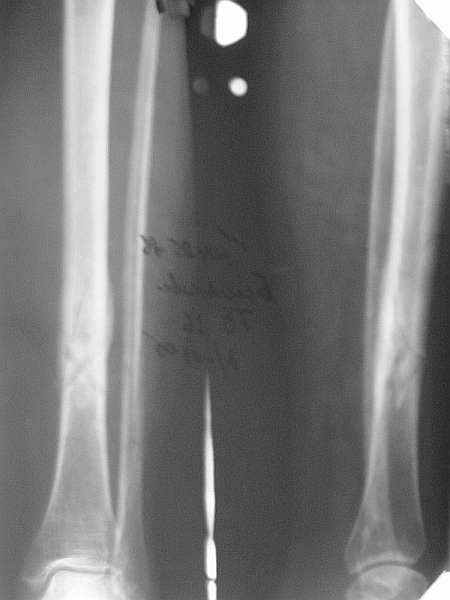

Типичный косо-спиральный перелом голени с низкой энергией, большеберцовая внизу, а сверху малоберцовая, и применение интрафрагментарного компрессионного шурупа можно оправдать, когда для

фиксации перелома выбран метод открытой фиксации пластинами, где пластина после стабилизации и компрессии перелома действует как нейтрализующая сила.

Без установки межфрагментарного шурупа, предпочителями отечественного метода Илизарова, дежурным аппаратом из двух колец при поступлении в приемном покое и на следуюший день двумя дополнительными спицами с напайкой за пределы фокуса решили бы проблему в два счета.

Такие изолированные (low energy trauma) переломы голени лечатся также гипсом, поэтапным консервативным методом Sarmiento, поэтому трудно согласиться с принятии метода, дать ему "право на жизнь" как стандарта для лечении при изолированных переломов голени.